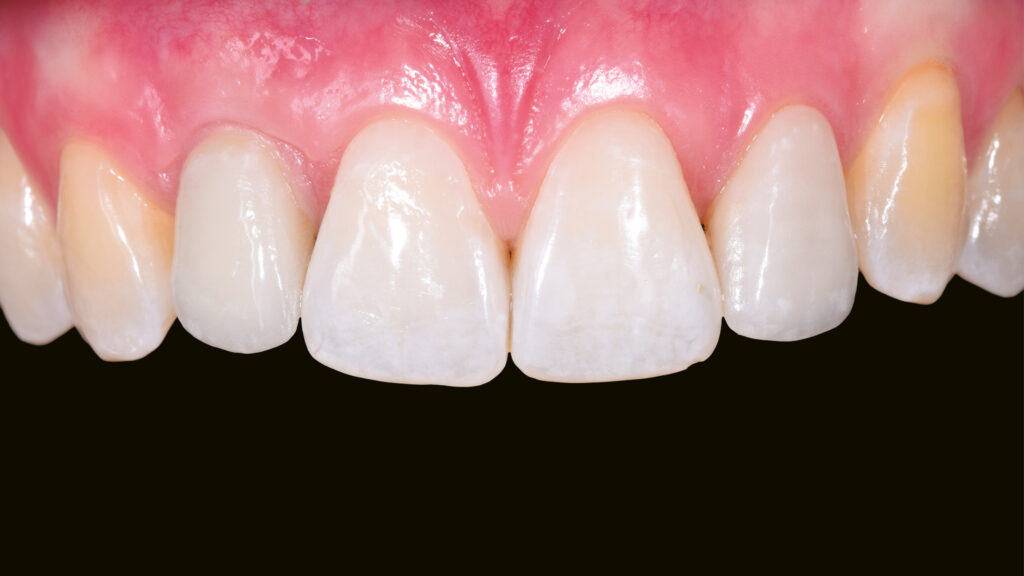

Ein Blick auf die Ausgangssituation (Abb. 1) verdeutlicht die Problematik bei diesem jungen Patienten. Der Milchzahn in regio 12 ist stark verfärbt. Zusätzlich beeinträchtigt der verkleinerte Zahn 22 (Mikrodontie) das ästhetische Bild. Auch der Gingivaverlauf erscheint unharmonisch. Abbildung 2 zeigt die Situation nach kieferorthopädischer Erstbehandlung. Während dieser Behandlungsphase konnte im Frontzahnbereich Platz für das Implantat (TiUltra, Nobel Biocare, Zürich, Schweiz) regio 12 und für das Keramikveneer an Zahn 22 geschaffen werden. Dies bildet die Grundlage für ein natürliches und harmonisches Erscheinungsbild.

Paradigmenwechsel:

Nach der Heilung des Weichgewebes sind die arkadenförmige Kontur der Gingiva und die Papillen deutlich zu erkennen (Abb. 42 und 43). Etwa sechs Monate nach der Osseointegration und Konditionierung der Gingiva wird die Situation mit dem Intraoralscanner erfasst, um mit der Herstellung der implantatprothetischen Versorgung fortzufahren. Nach dem Aufschrauben des Scanbodys auf das Implantat erfolgt der Scanvorgang (Abb. 44). Intraoralscanner gehören zu den aufregendsten neuen Technologien in der Zahnmedizin. Die digitale Abformung bietet dem Patienten deutlich mehr Komfort. Zudem werden klinische Abläufe vereinfacht und die Kommunikation mit dem Zahntechniker verbessert. Im nächsten Schritt werden die STL-Dateien für den Modelldruck aufbereitet (Abb. 45). Vor dem Scannen der gedruckten Modelle muss das Modellanalog regio 12 eingesetzt werden. Das Modell mit abnehmbarer Gingivamaske ist für die Aufnahme des Modellanalogs durch eine Öffnung vorbereitet und besitzt im unteren Bereich des Ausschnittes eine Art Verriegelungsmechanismus (Abb. 46). Dies gewährleistet einen sicheren Presspassung und eine korrekte, automatisch zentrierte Einschubposition (Abb. 47).

Abschließend kann der Schraubenkanal mit Teflonband und Komposit verschlossen und die statische und dynamische Okklusion überprüft werden. Bei der Eingliederung einer Frontzahnimplantatkrone kommt es vor allem auf eine ästhetische Integration an. Neben der weißen Ästhetik ist die rote Ästhetik mit der Ausformung des Emergenzprofils und der Harmonie des Gingivaverlaufs wichtig. Die Restauration fügt sich ästhetisch gut in die Zahnreihe ein (Abb. 66 bis 68). Das Zusammenspiel der dentalen und gingivalen Umgebung sowie der Lippen mit der prothetischen Versorgung ergibt ein harmonisches Gesamtbild (Abb. 69). Einige Monate nach dem Einsetzen der Implantatkrone hat sich die Gingiva sichtbar gut erholt (Abb. 70).